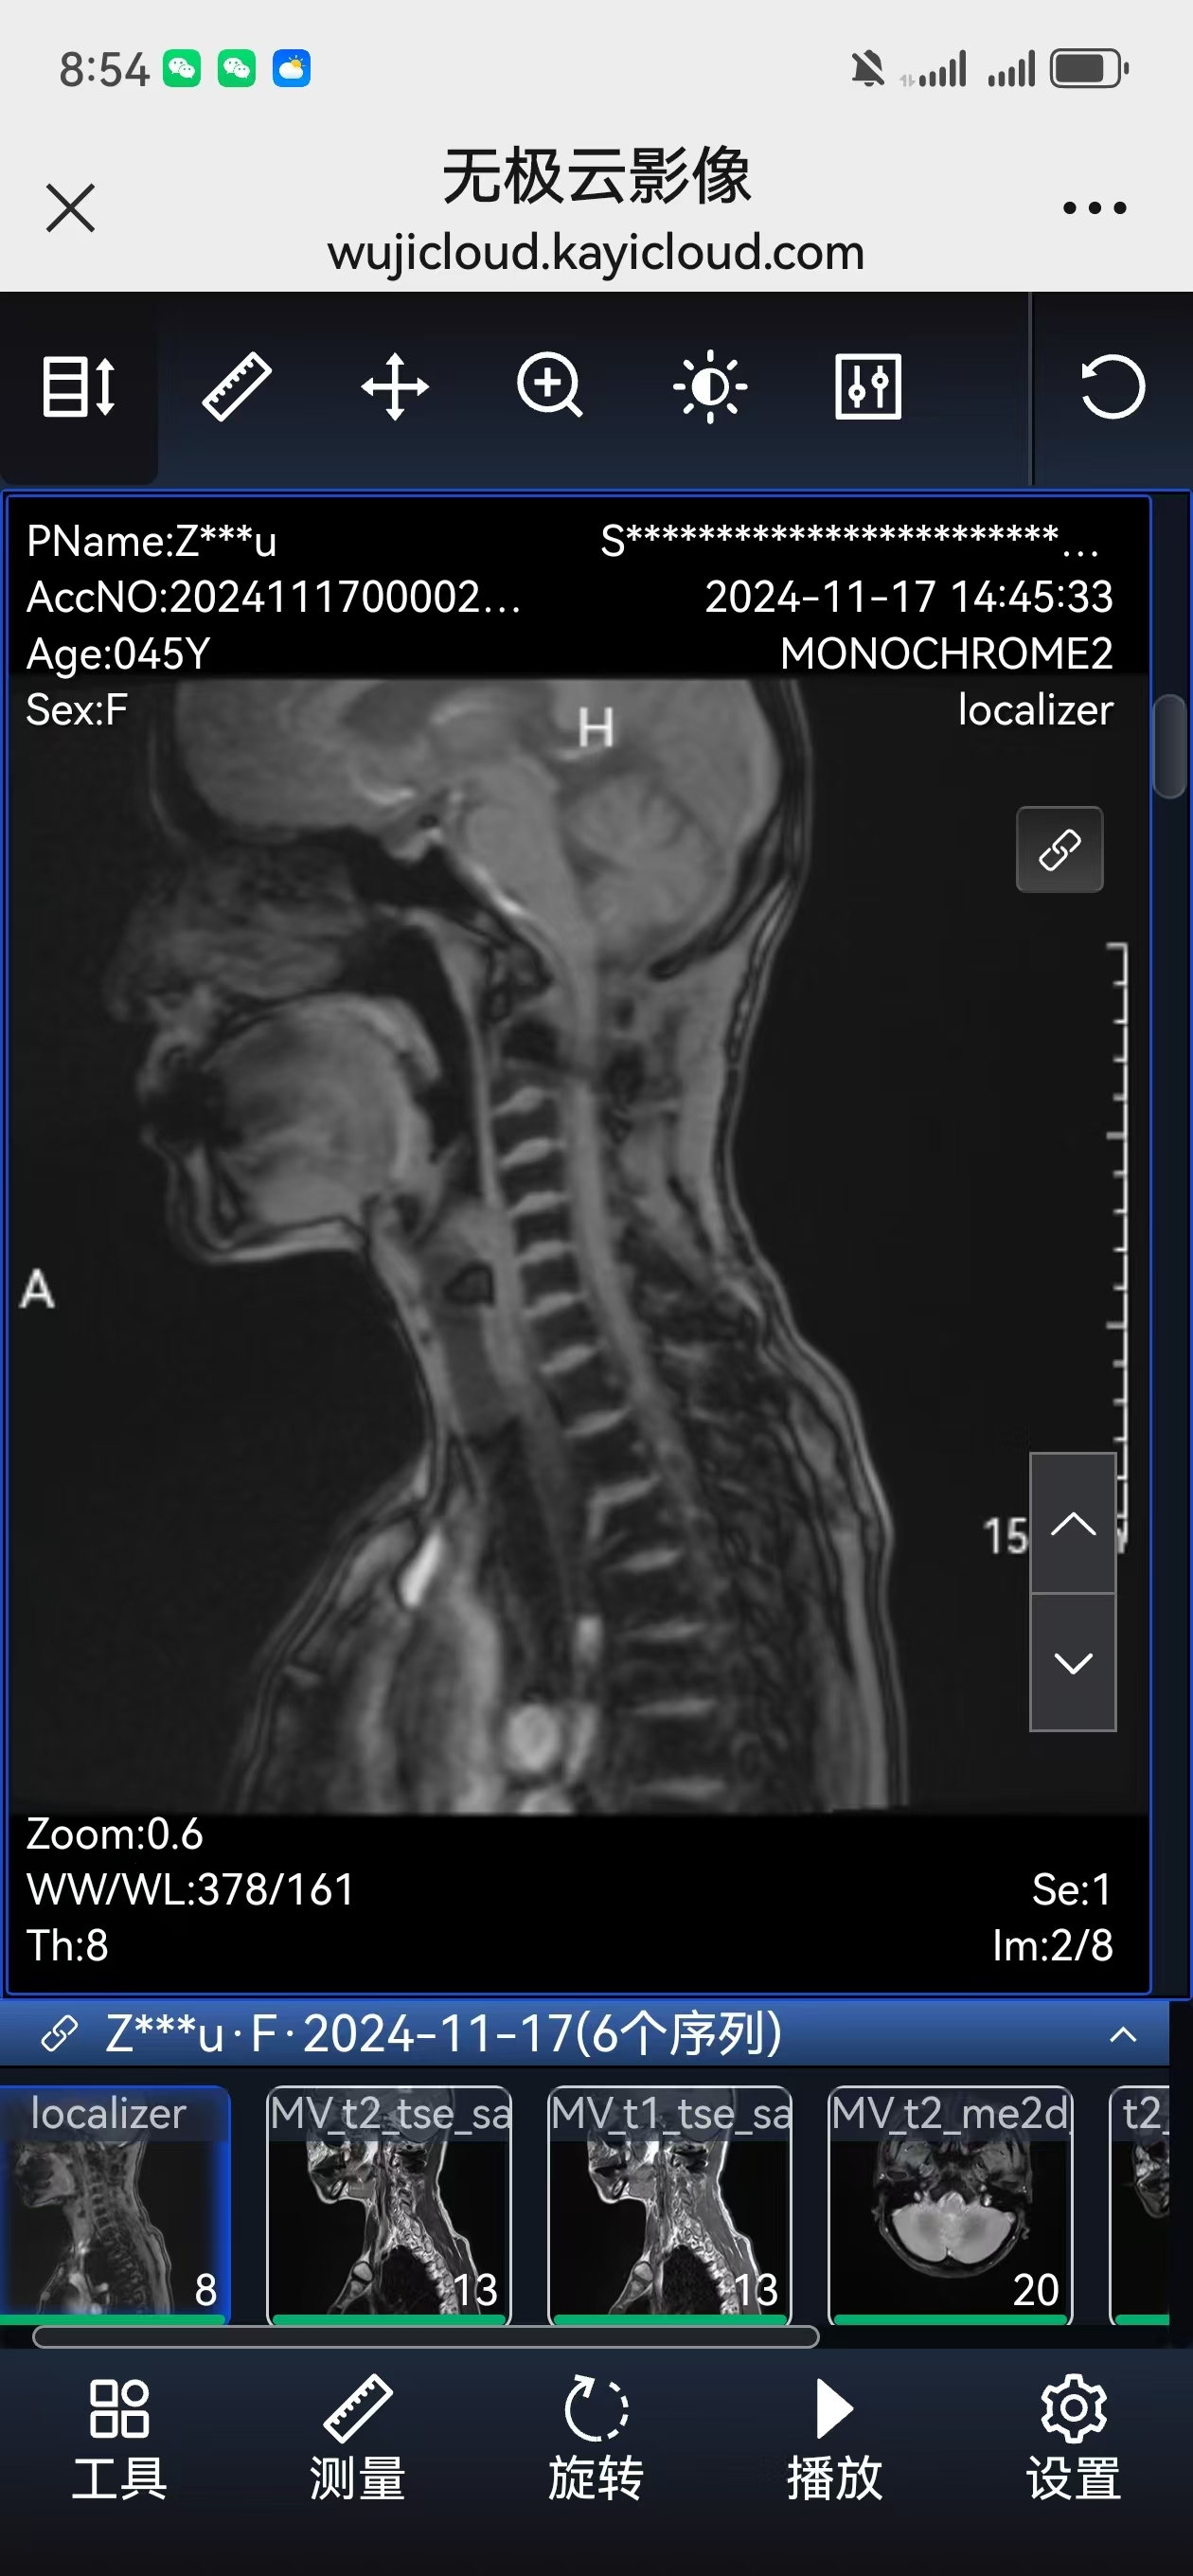

• 术后影像: